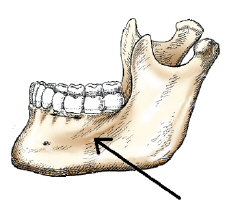

body

axiolateral oblique of the mandibular body

how is the head positioned to demonstrate the body of the mandible in the axiolateral oblique projection

30 degrees toward the IR

which positioning line must be aligned perp to the IR for the PA mandible

OML

ramus

how must the head be positioned to best demonstrate the ramus of the mandible in an axiolateral projection

lateral